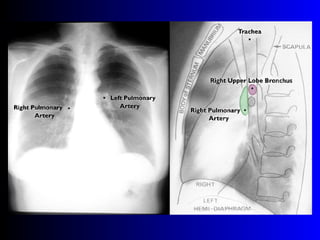

Este documento describe la técnica para realizar una telerradiografía de tórax normal e identifica las estructuras visibles en la imagen, incluyendo los huesos, vasos sanguíneos, grasa, tejido subcutáneo, pulmones y mediastino. Explica que es importante centrar la imagen en los ápices pulmonares, senos costodiafragmáticos e inspiración profunda para una visión clara de las estructuras.